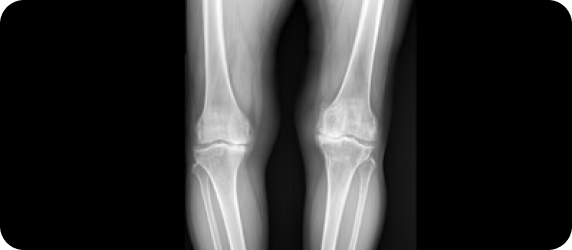

골반

1. 골반이 앞으로 기울어진 골반전방경사

2. 골반이 뒤로 기울어진 골반후방경사

3. 골반 한쪽이 아래로 내려간 골반 좌우불균형

4. 엑스레이 검사상 좌우골반의 크기가 다르게 보이는 골반 회전

5. 여러 가지 틀어짐이 동시에 존재하는 골반 복합 불균형

예시 ) 골반전방경사 + 골반좌우불균형 + 골반회전

골반이 앞으로 기울어진 골반전방경사가 있다면 보행 또는 선자세에서 무릎 앞쪽의 연골에 체중이 집중되기 때문에 무릎 연골 손상이 더 빨라집니다. 또 한쪽으로 회전되고 기울어진 골반은 기울어진 쪽으로 상체의 체중이 집중되어 무릎 연골 손상을 가속화 시킵니다.

▲ 무릎 수술환자의 스캐노그램 엑스레이 검사